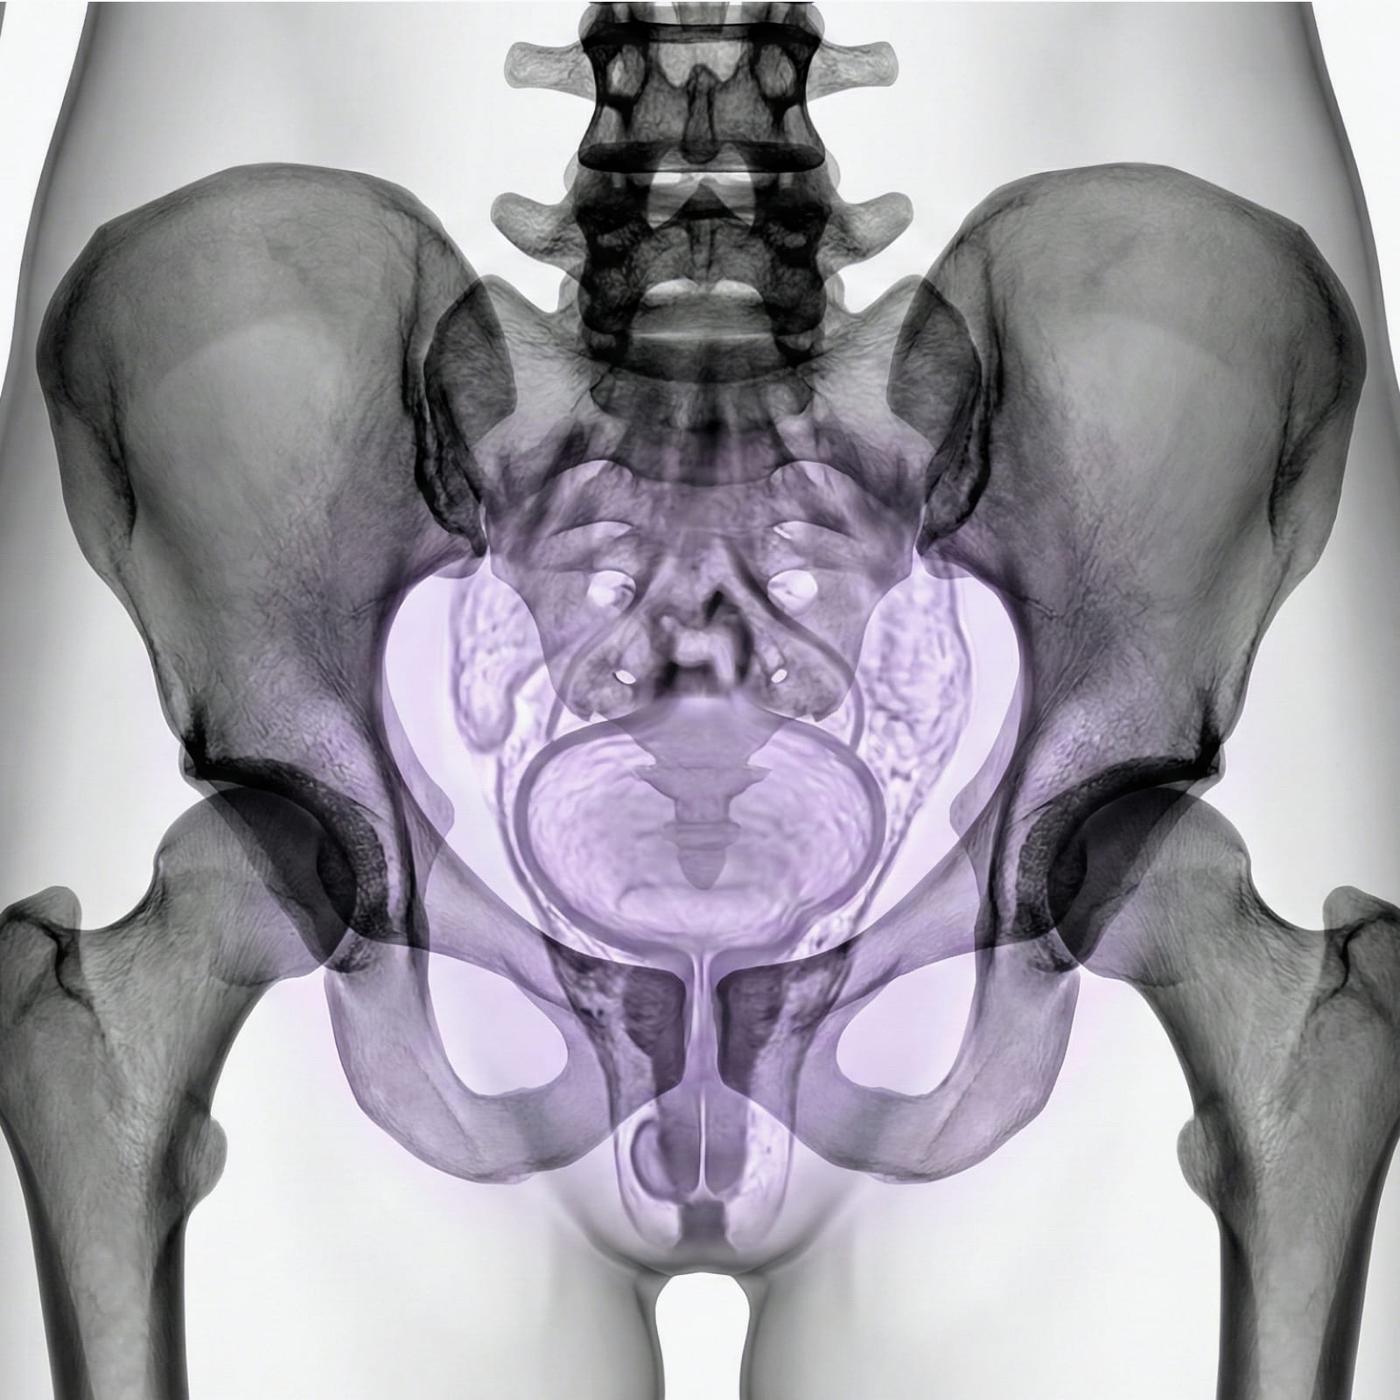

Om du har ont i nedre delen av magen, oregelbundna blödningar, problem med fertiliteten eller misstänker att något inte står rätt till i underlivet så kan en MR-undersökning av lilla bäckenet vara ett nästa steg för att få rätt diagnos. MR Lilla bäckenet, även kallad MR gynekologi, är en smärtfri och strålningsfri undersökning som ger mycket detaljerade bilder av både livmodern, äggstockarna och äggledarna.

Undersökningen används när andra metoder som ultraljud eller gynekologisk undersökning inte har kunnat förklara dina symtom. Med hjälp av MR kan man upptäcka tillstånd som endometrios, myom, cystor, tumörer, missbildningar eller påverkan på närliggande organ som urinblåsa eller tarm. Det är också en viktig metod inför fertilitetsbehandling eller som förberedelse inför kirurgi.